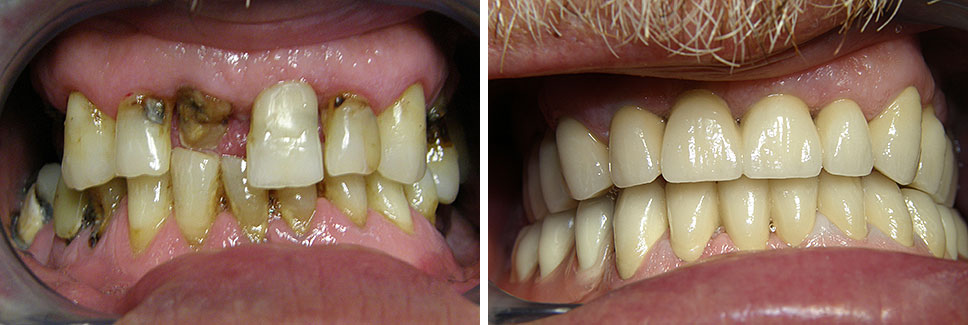

Estetska dentalna medicina